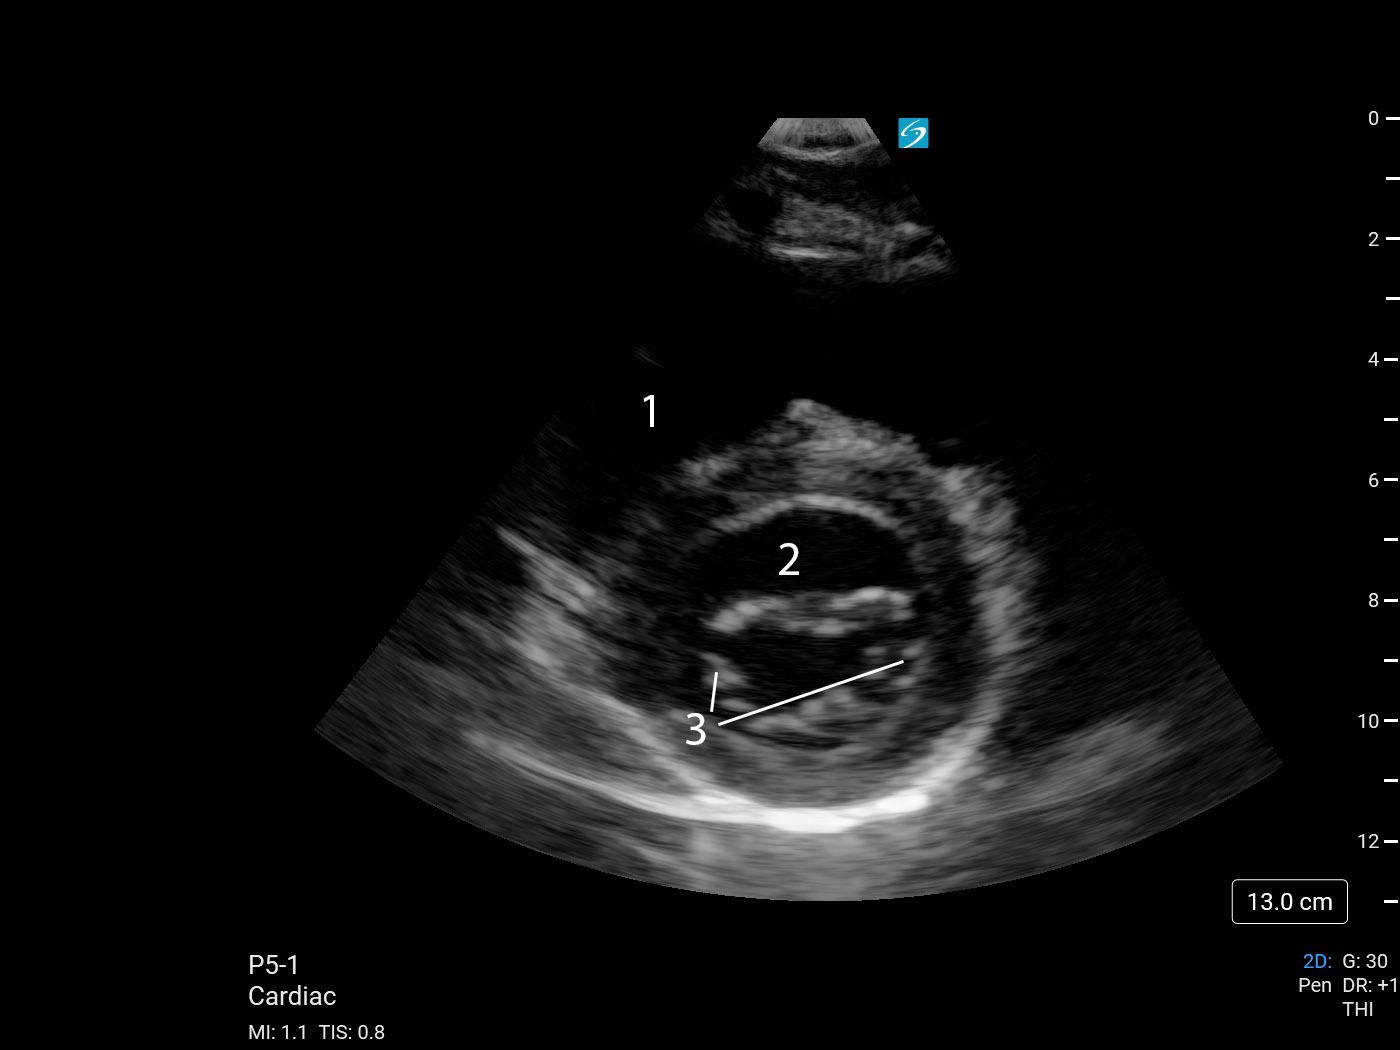

Heart Parasternal Short Axis (PSAX) (Sonosite PX P5-1) 1 Image

1. Right Ventricle (RV)

2. Left Ventricle (LV)

3. Valves